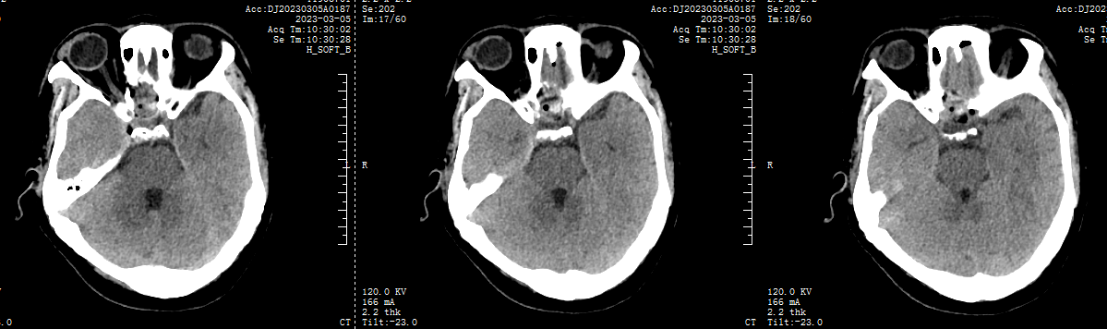

2.两天前患者无诱因出现头晕,伴恶心、呕吐、右眼视物模糊,无意识障碍,无发热、咳嗽、咳痰,无耳鸣、听力下降,无言语不清、饮水呛咳、吞咽困难,无颈强直,无肢体感觉及活动障碍等伴随症状,于我院门诊就行头颅CT示:腔隙性脑梗死,现为进一步诊治,遂来我院。

术后CT